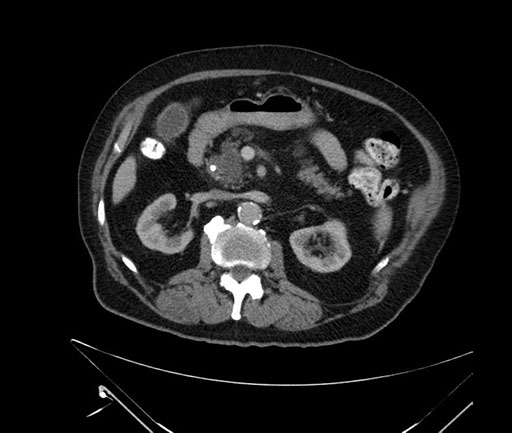

Axial - 3 months prior